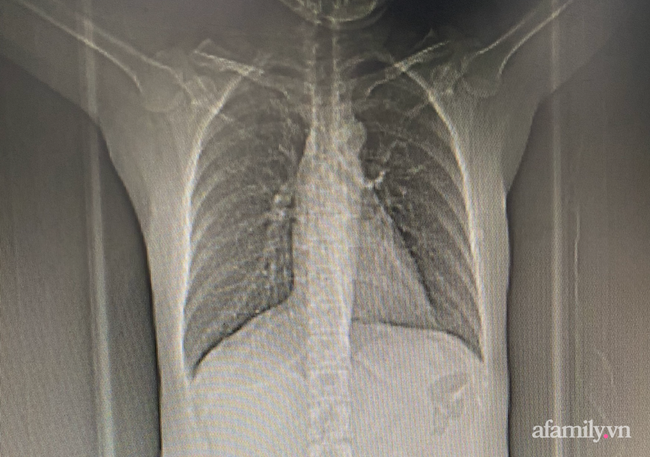

Sau khi chúng tôi đăng tải bài viết phản ánh sự việc chị N.T.M.C. (43 tuổi, ngụ quận Thủ Đức, TP.HCM) phải cắt bỏ ngực phải dù được BV Ung bướu TP.HCM chẩn đoán lành tính 1 tháng trước, bác sĩ đang tiếp nhận điều trị cho bệnh nhân tiếp tục có những ý kiến xoay quanh câu chuyện cung cấp hồ sơ bệnh án.

Trong quá trình điều trị, tóm tắt bệnh án không thể thay thế việc đánh giá trực tiếp trên những xét nghiệm, ảnh phim hay MRI của bệnh nhân. Nếu không cung cấp ngay các hình ảnh chẩn đoán cho bệnh nhân sẽ gây khó khăn cho bệnh nhân và cả bác sĩ khi nhận bệnh từ nơi khác đến.

Dẫn chứng hậu quả của việc không trả ngay các xét nghiệm cho bệnh nhân, bác sĩ Vũ chia sẻ trước đây từng có 1 bệnh nhân tên C.T.N. bị ung thư phổi, điều trị tại BV tuyến trên rồi chuyển về BV quận Thủ Đức.

Vì phải xin tóm tắt bệnh án rồi tiếp tục làm tiếp đơn xin sao chụp các hình ảnh xét nghiệm nên việc chẩn đoán, điều trị của bác sĩ gặp rất nhiều bất lợi. Sau đó, bệnh nhân đã mất.